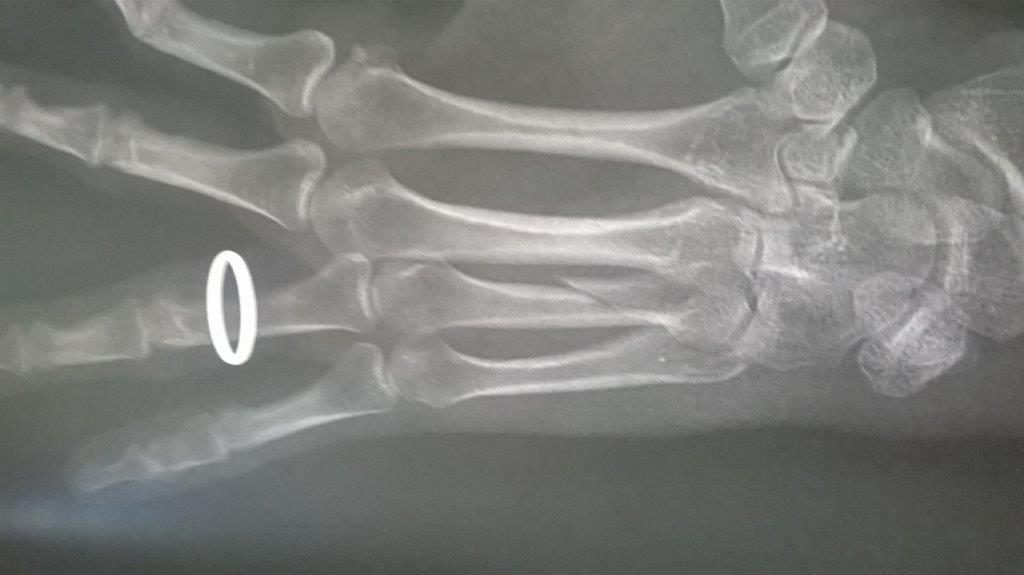

Résultat : fracture de la main gauche

WP_20170914_001.jpg [ 47.5 Kio | Vu 29219 fois ]

Mais je confirme que ma saison de triathlon s'achève aujourd'hui. Main gauche immobilisé. Je suis au regret de déclarer forfait pour Paladru et d'abandonner les Mixirilliettes à leur triste sort